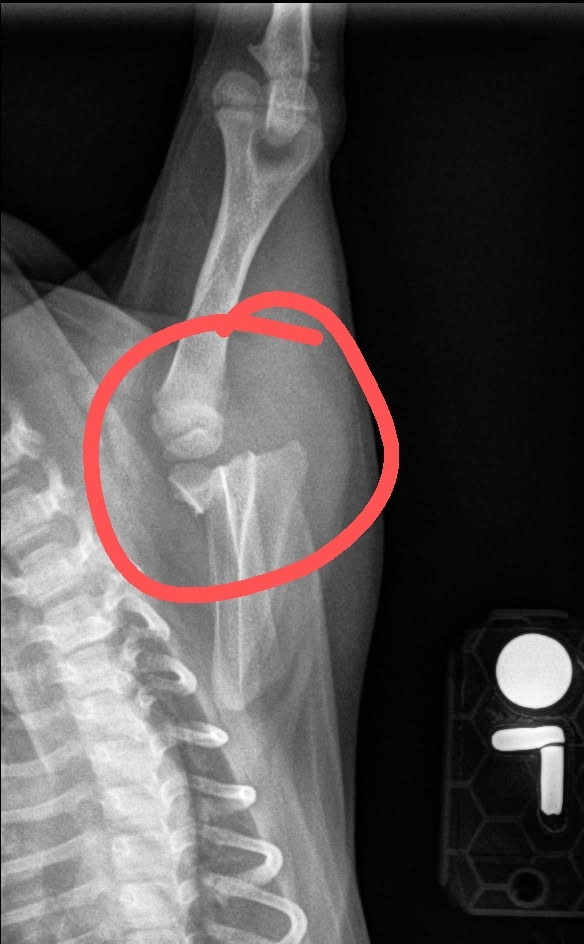

We took her to the vet, and the first location performed x-rays and told us it was a shoulder luxation and directed us to seek further evaluation. We immediately went to a 24-hour emergency animal hospital and was shocked to find out after further testing that her left shoulder was broken. We were devastated to say the least. We want to get her immediate care, but due to the insurance waiting period and are current living situation, we are stuck with a bill that we cannot afford. The bill is estimated to be upwards of $9000 on top of the previous vet and hospital expenses that we have already paid for. Thai tea needs an immediate scapula body fracture closed procedure.